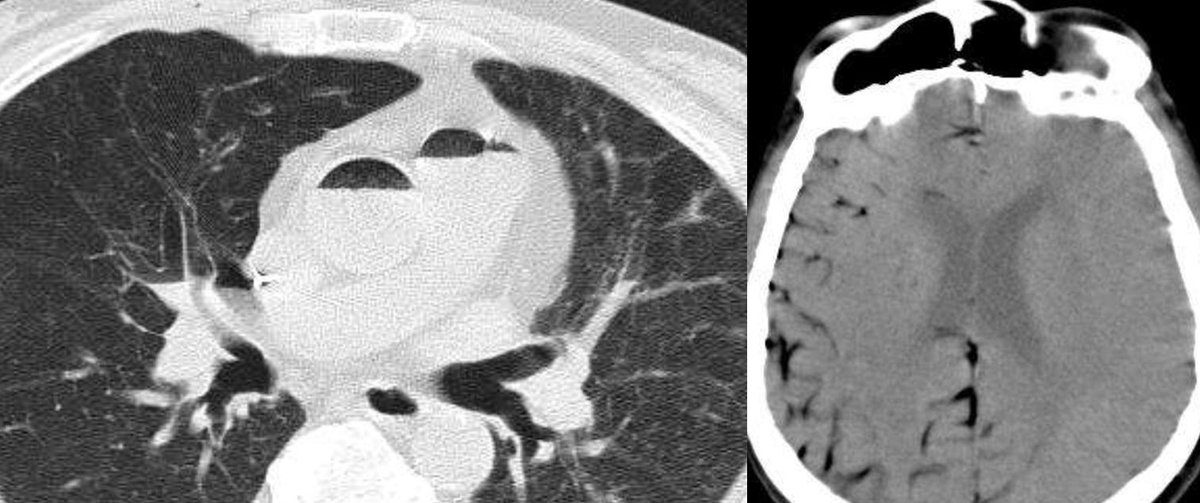

Benveniste and colleagues describe how to distinguish changes expected after radiation therapy for thoracic malignancies from complications such as infection and radiation-induced malignancy: https://bit.ly/2tWSziq

#ChestRad pic.twitter.com/eL3vkgckoI